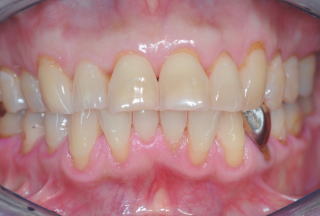

当Clinicでは、すべてInterdisciplinary Treatment(包括的治療)を基本にしている。患者は38年間当Clinicで口腔管理をしている症例

である。開業当初から当診療システムで38年間口腔管理をしている。Panorama、CTなどレントゲンを介しての顎骨・歯槽骨の形態・骨

量などを観察したもので、歯槽骨の吸収状態から診ても、ほぼ二十歳代に相当するように思われる。過去の論文を見ても、口腔内写真

患者:83歳、女性

(図15)2015年7月27日、83歳。高年齢と残存歯数ばかりが問題視されているが、歯槽骨の状態、歯肉、Pocketの状態を含めた歯周病を評価すべきである

歯周病治療38年経過:83歳(女性)残存歯数28本